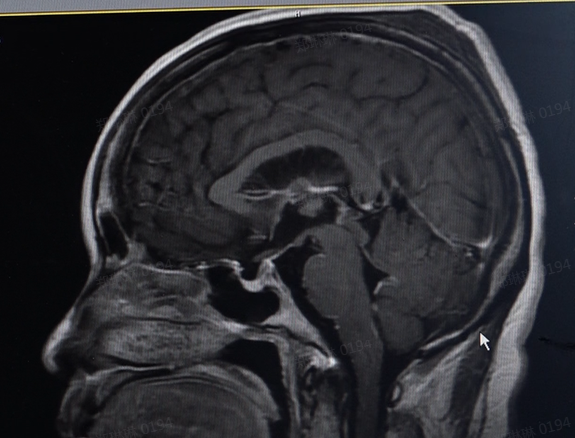

患者影像片显示,颅内有脑膜广泛强化,提示存在颅内感染。